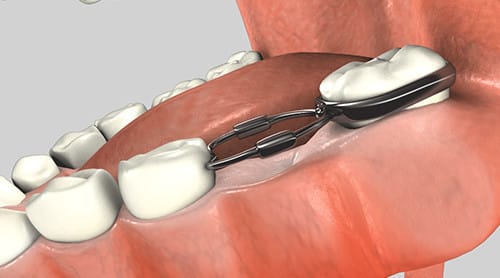

Some orthodontic problems can be fixed with the use of an orthodontic appliance such as a retainer or space maintainer. We offer some of these appliances as an alternative to or in addition to standard orthodontic treatment.